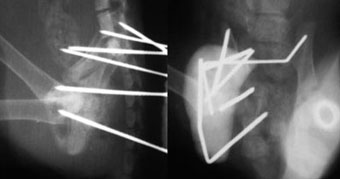

猫の骨盤骨折もプレート法により整復固定するのが一般的ですが、骨盤が薄いため

スクリューによる固定力が弱くプレート脱落をおこしやすく、とくに骨の柔らかい仔猫では

手術が困難でした。

当院では、猫の骨盤骨折を創外固定で整復することでこれらの問題点を克服するとともに、

患猫の手術負担の軽減にも成功しています。

他院からの依頼症例

体重3kg、5歳齢の猫。

腸骨体と恥骨骨折および仙腸関節離断をおこしていました。

写真上段: 手術前

写真中段: 手術後

6本の創外固定ピンを刺入して骨盤構造を支えています。

写真下段: ピン抜去後

骨盤構造は正常に近い状態に回復しています。 |